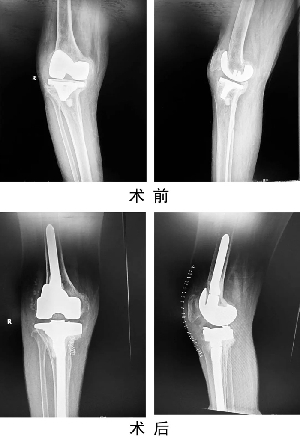

我院成功開展人工關(guān)節(jié)假體周圍感染一期翻修手術(shù)

關(guān)節(jié)運動醫(yī)學(xué)二科蘇長征團隊,在我院首次成功開展人工膝關(guān)節(jié)假體周圍感染一期翻修術(shù),標(biāo)志著我院關(guān)節(jié)置換手術(shù)技術(shù)又上新臺階。患者,女,69歲,因“右膝人工關(guān)節(jié)置換術(shù)后6年,疼痛伴活動受限1年”入住關(guān)節(jié)運動醫(yī)學(xué)二科。術(shù)前X線示右膝人工關(guān)節(jié)假體松動,感染指標(biāo)檢查:C反應(yīng)蛋白80mg/L,血沉20mm/h,關(guān)節(jié)穿刺培養(yǎng)提示表皮